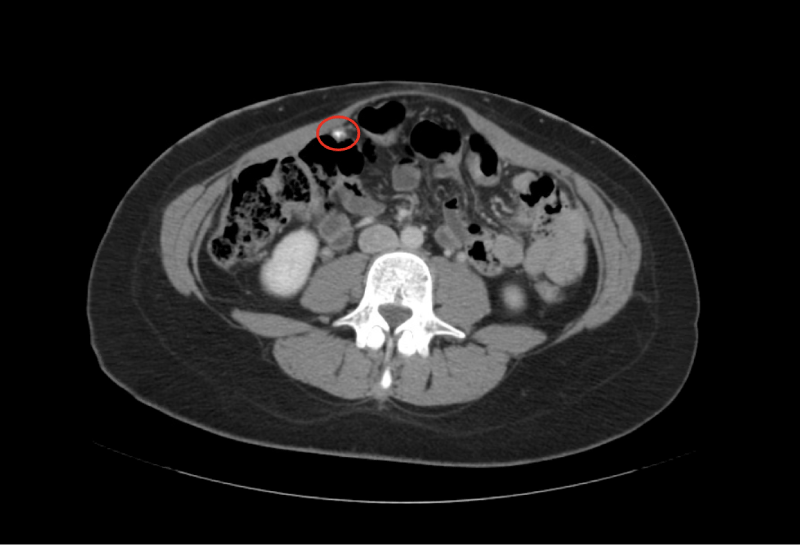

The patient is a 25-year-old white primigravid female at 41.1 weeks gestation. The pregnancy was complicated by failure of 1 hour glucose tolerance test (GTT) with refusal of 3-hour GTT. Ultrasonography at 35 and 6/7 weeks indicated the fetus was large for gestational age (LGA) but did not otherwise indicate any abnormalities, including the presence of abnormal uterine, adnexal, or pelvic organ abnormalities. She presented to labor and delivery from a birthing center for prolonged labor and prolonged rupture of membranes. Despite Pitocin augmentation, uterine contractions were inadequate and transition to cesarean delivery was recommended for failure to progress. A healthy male infant was delivered via C-section. Uterine atony was noted. Quantitative blood loss was 1326 mL, conferring a diagnosis of postpartum hemorrhage. This was managed successfully with intraoperative methergine administration. Abnormal intraoperative findings included uterine, bladder, abdominal wall, and omental nodules. A uterine nodule biopsy was obtained intraoperatively and sent to pathology, where it was initially identified as a low-grade serous neoplasm. The tumor immunohistochemistry is shown in table 1. The patient and her baby progressed through the acute postpartum period without further sequelae and were discharged home on postpartum day 2. On postpartum day 18, the patient underwent a computed tomography (CT) scan which revealed multiple partially calcified masses seen primarily in the parametrial fat which were suggestive of peritoneal based disease. Imaging studies are shown in figures 1a-1c. The patient’s care was transferred to a gynecologic oncologist, where she completed six cycles of Lupron Depot and anastrozole chemotherapy in addition to an omentectomy and a total abdominal hysterectomy with bilateral salpingo-oopherectomy. At the time of this case report, the patient is receiving combination therapy which includes traditional chemotherapy and “integrated holistic therapy” coordinated by an independent clinic in California. The information described in this case summary was collected via direct involvement in the case and thorough chart review.

Figure 1a: Computed Tomography demonstrating partially calcified peritoneal mass at the lateral margin of the right colon proximal to the hepatic flexure. View Figure 1a